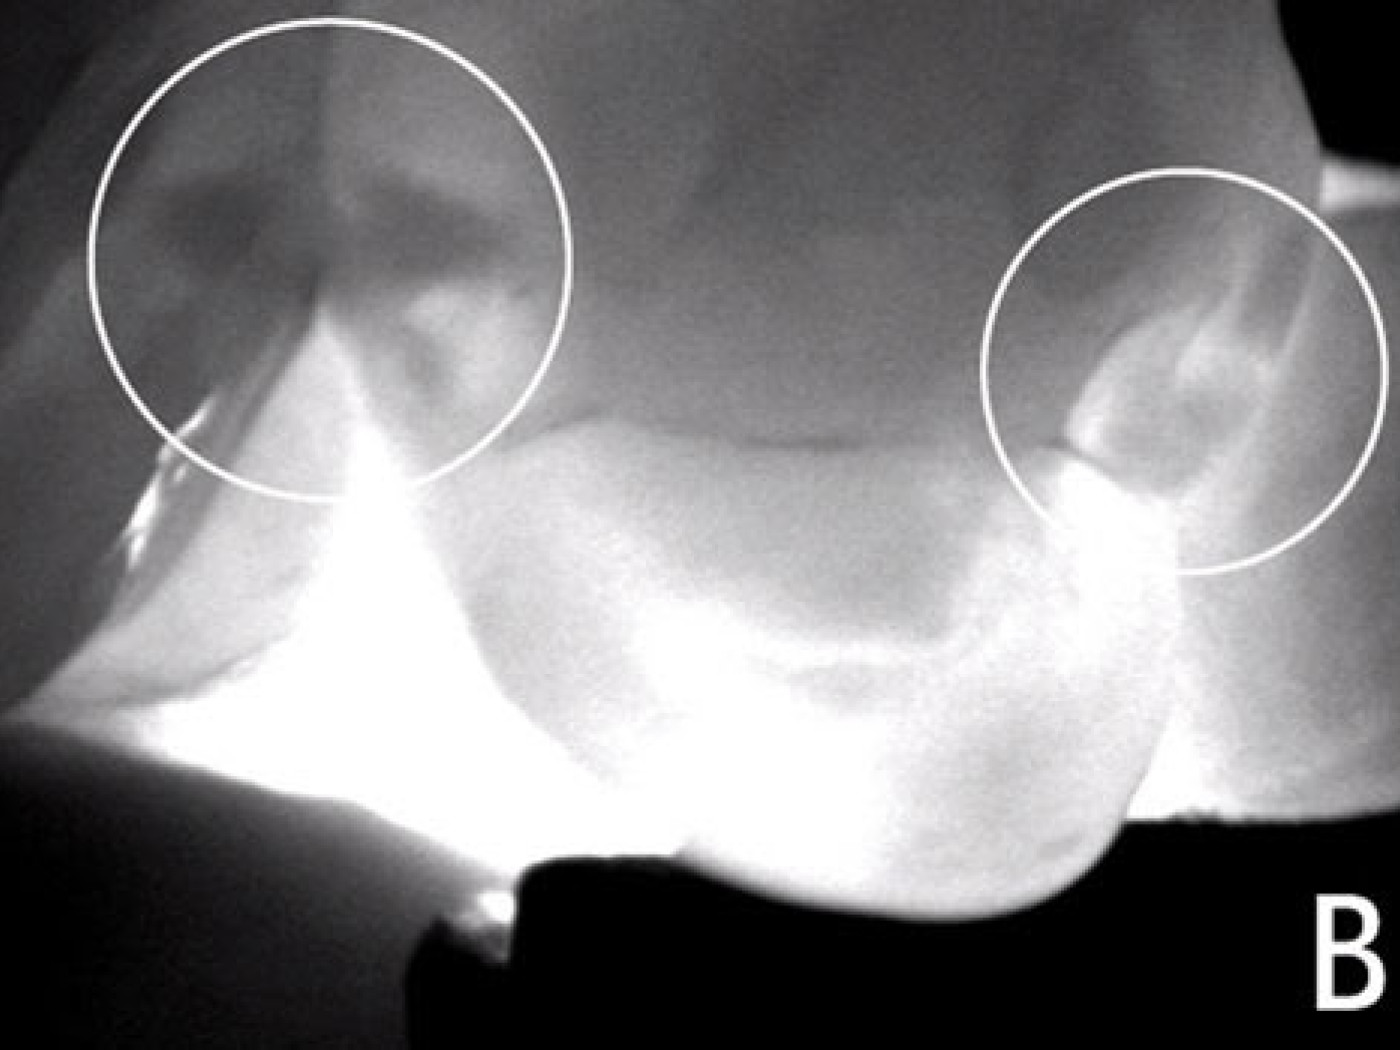

На рис. (А) представлены премоляры, которые кажутся клинически здоровыми. Затемненные участки заметны только на рисунке (B) (левый и правый круг), полученном при помощи DIAGNOcam. Кариозные изменения также заметны на рентгеновских снимках на задней поверхности. С помощью рентгеновского излучения переднюю область зуба оценить не всегда возможно в связи с эффектом частичного наложения (C), которое возникает довольно часто.